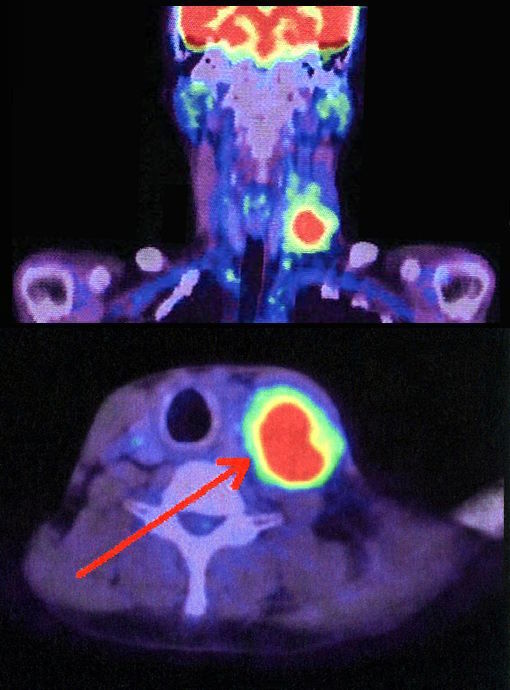

HNSCC představuje skupinu nádorů, které vznikají ve slizničních buňkách v oblasti krku, nejčastěji postihují ústa, hrtan, nosohltan a hltan. Nádory ústní dutiny a hrtanu jsou obecně spojovány s nadměrnou konzumací tabáku a/nebo alkoholu, zatímco nádory hltanu jsou stále častěji připisovány infekci lidským papilomavirem (HPV), primárně HPV-16. Mezi nejčastější příznaky této formy rakoviny patří nehojící se vředy v ústech, změny hlasu, potíže s polykáním, červené či bílé skvrny v ústech a bulky v oblasti krku.

Studie Orig-AMI 4, financovaná farmaceutickou společností Janssen, zahrnovala pacienty z 11 zemí, kteří trpěli recidivujícím nebo metastatickým dlaždicobuněčným karcinom hlavy a krku, a to obtížně léčitelnou formu, která se často vrací i po standardní terapii.

Skupina 86 pacientů ve studii, kteří již dříve podstoupili imunoterapii a chemoterapii, dostávala amivantamab. U 76 % z nich došlo ke zmenšení nádorů, případně k zastavení jejich růstu, a to zpravidla do šesti týdnů od zahájení léčby, které byla obecně dobře snášena.